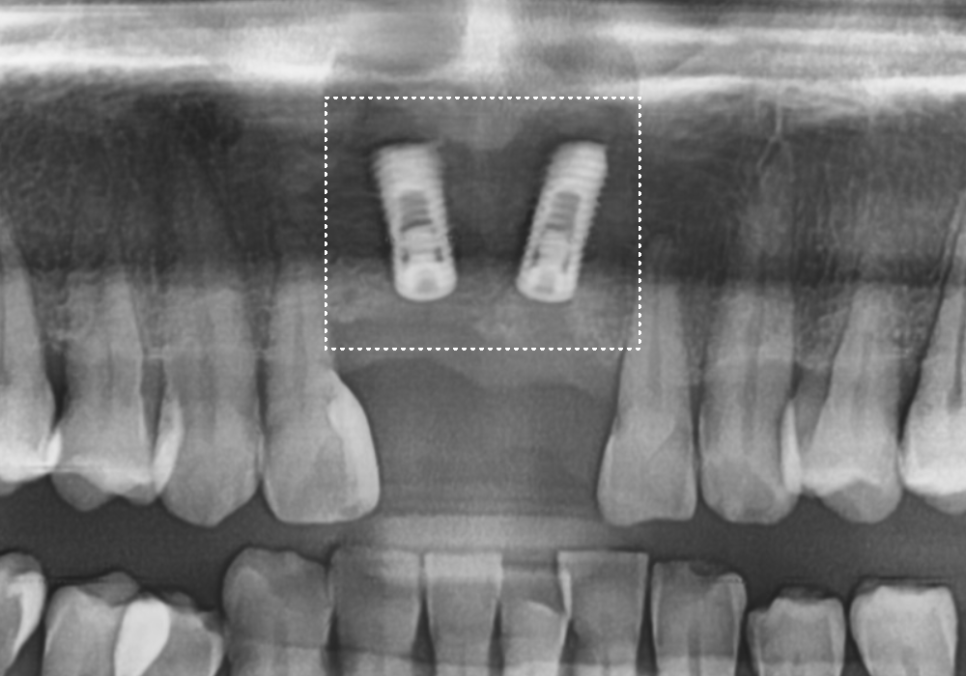

입안을 살펴보니, 오른쪽 앞니(#11)는

이미 부러져서 뿌리만 남은 상태였고,

왼쪽 앞니(#21)는 동요도 3도로

확인될 만큼 심하게 흔들리고 있었습니다.

240523

230524

잇몸뼈가 치아를 거의

잡아주지 못하는 단계라

뿌리만 남은 치아와 흔들리는 치아 모두

발치가 불가피했습니다.

환자분의 경우 빠진 치아 옆 치아마저(#12)

약간 흔들리고 있어서,

브릿지로 하기엔 무리가 있었어요.